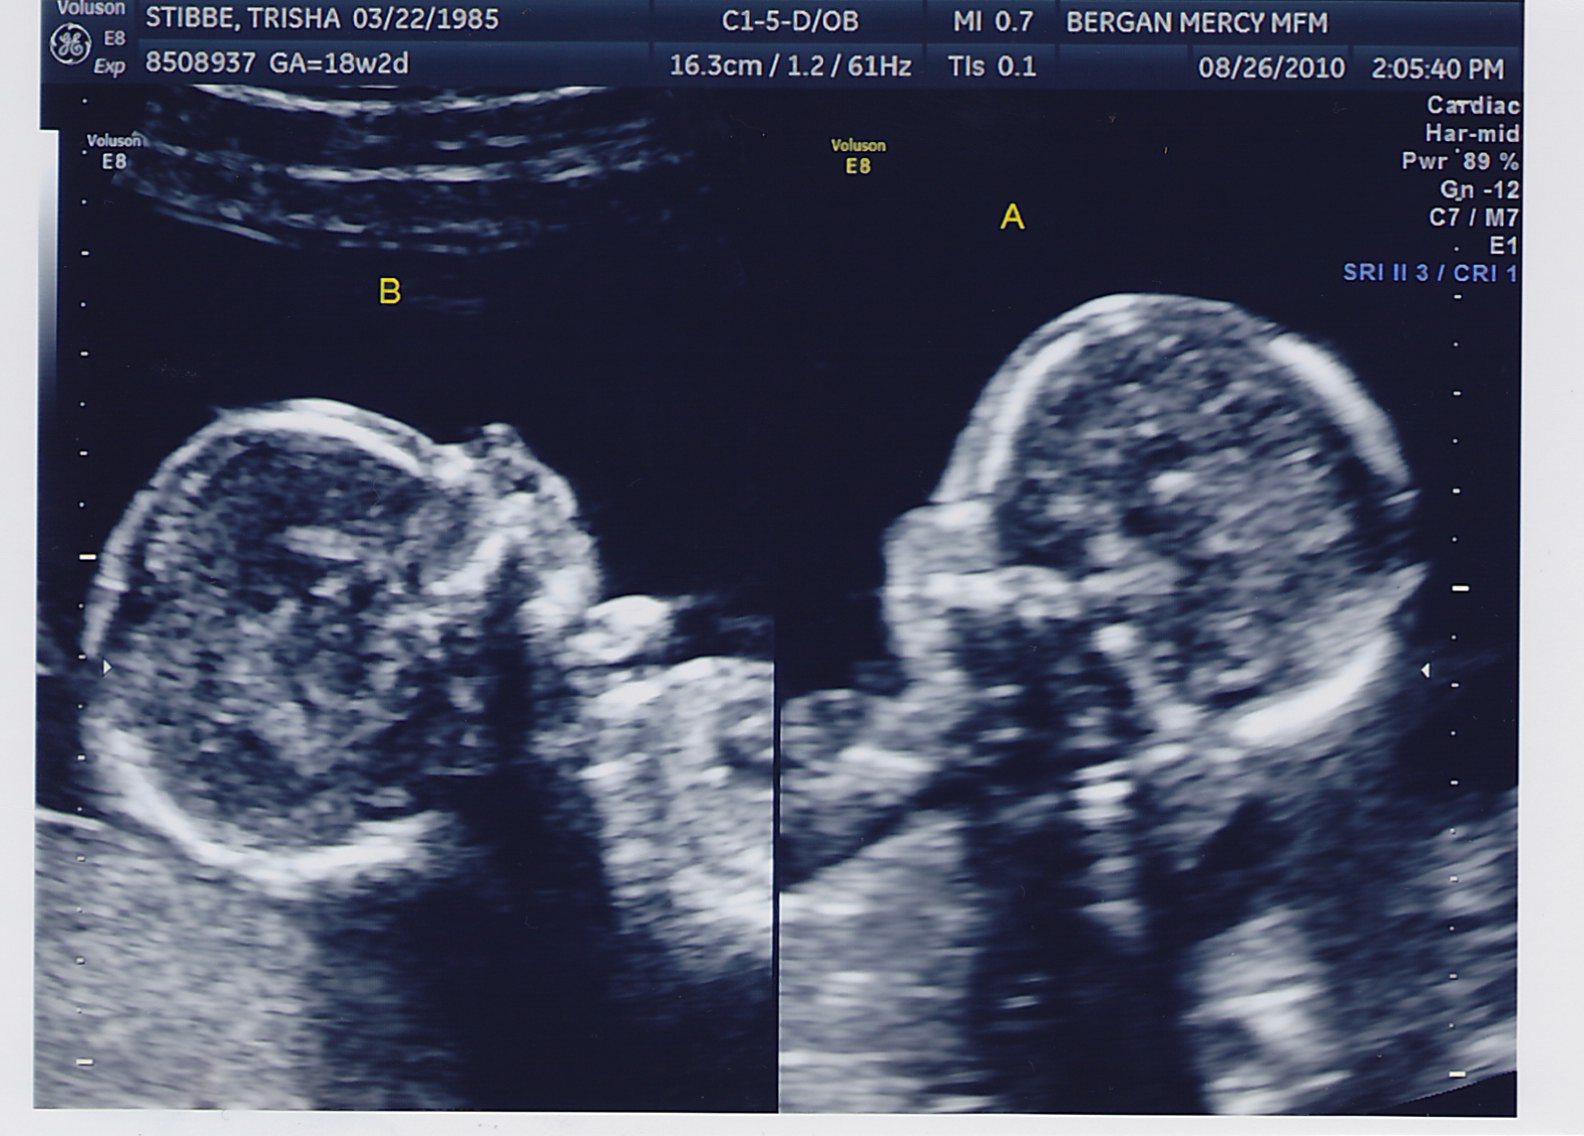

The ultrasound tech was able to do a cool screen shot this time- here’s what they look like in Week 18.